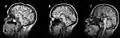

Image du corps calleux en coupe sagittale(plan vertical, orienté d'avant en arrière) en IRM (imagerie par résonance magnétique).

IRM révélant une agénésie du corps calleux.